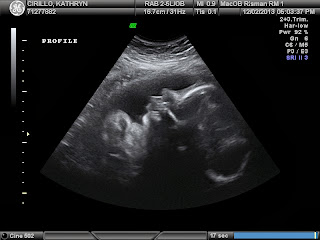

I don't think my words can begin to express how grateful I am for this miracle to be coming into our family in less then 2 months. I cried tears (happy tears) as our sweet ultrasound tech brought these pictures up. She knew how exciting of a time for us this was and she allowed us to enjoy every second. After she left the room and we were waiting for the Dr. to come in, she left the last picture up on the big screen in the room so we could continue to be in awe of it. Cue some more tears at this point, I just can't believe how perfect this little boy is.

Now on to the health stuff... Sam weighs 4.5lbs at 33 weeks. Weight in range= check. Mom's fluid levels being in normal range= check. I was worried about the fluid levels which can be indicative of a concern with my blood pressure if they are too high. Need not to worry about that! Sam's organs measuring properly and in range= check. Then as we are reassured every single ultrasound... his esophagus and stomach are attached = CHECK CHECK CHECK!